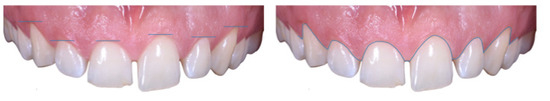

Case Report